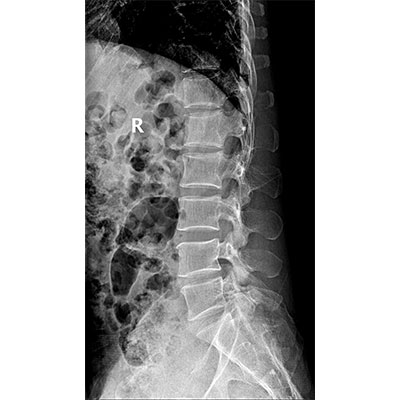

以微知形 為愛負責 微劑量 極速曝光 PLX8500E/F

● 短曝光、高熱容,拍片數量多、效率高。

● 輕松應對大型體檢中心高強度的拍片要求。

● 采用自主研發的技術,在保證優質圖像的前提下,大大降低X射線劑量,用心呵護醫護工作者及患者的健康。

● 短曝光時間,便于老年人、兒童、殘疾人進行臨床拍攝。避免這類群體因不能有效控制身體運動等因素造成的運動偽影,提高攝片質量及效率。